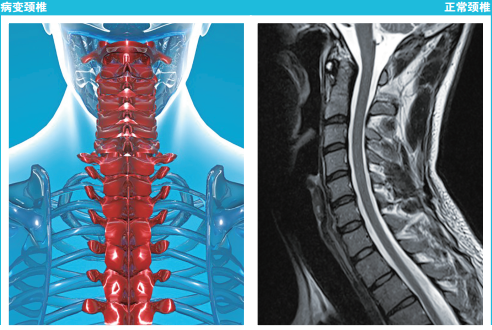

最常见的两种类型的颈椎病分别是神经根型颈椎病以及脊髓型颈椎病。在薛先生的《告全国低头族同胞书》中,有一张颈椎核磁共振的图像。我们借着这张图,先来看一下颈椎的解剖结构。

颈椎是位于身体中间偏后脊柱的最开始一部分,与头颅的底部相连,可见其重要程度。颈椎由七块骨头(颈椎椎体)组成,其中第一节与第二节骨头形态不规则 (在图像中,由于扫描层面原因第一颈椎显示不清)。第三到第七节颈椎椎体在这张核磁共振图像中近似于长方形。椎体和椎体之间黑色间隙部分就是我们经常能听到的椎间盘。我们再向后方看(图像右侧),有纵行白-黑-白的条状结构。黑色的结构是与脑组织相连的脊髓,前后两层白色结构是围绕在脊髓四周的液体结构——脑脊液。脊髓和脑脊液存在的空间被称为椎管。

在图像中,薛先生的第四、五节段和第五、六节段水平(被薛先生用红圈圈起来的位置),椎体后方的白色脑脊液信号消失,黑色的椎间盘直接压迫脊髓组织,引起局部脊髓的变形。这时就可能引起神经症状。通常,颈椎病发生在颈4到颈7节段,这也被称为低位颈椎。高位的颈椎负责头部的旋转运动。而低位颈椎负责头部的屈伸运动,也就是我们平日里说的低头和抬头。所以长时间的低头和颈椎病的发生有着不可回避的责任。

在薛先生的核磁共振图像中,还有一点非常令人注目的异常就是颈椎的曲度,也就是七节颈椎椎体的整体排列关系。我们常常会听到某人从医院检查回来说“颈椎反弓”,这就是一种曲度的排列异常。

在生理状态下,颈椎的排列关系应该成为一条向前(嘴的一侧)突出的曲线,前突的角度约为20-35度。薛先生的颈椎虽然没有严重到“反弓”的程度,但是颈椎前突的角度消失了,成为了一条僵直的直线。长时间保持低头姿势引起的颈部肌肉和韧带退变是颈椎前突消失的重要原因。而颈椎生理前突的消失也成为引发进一步更为严重颈椎病理改变的基础。